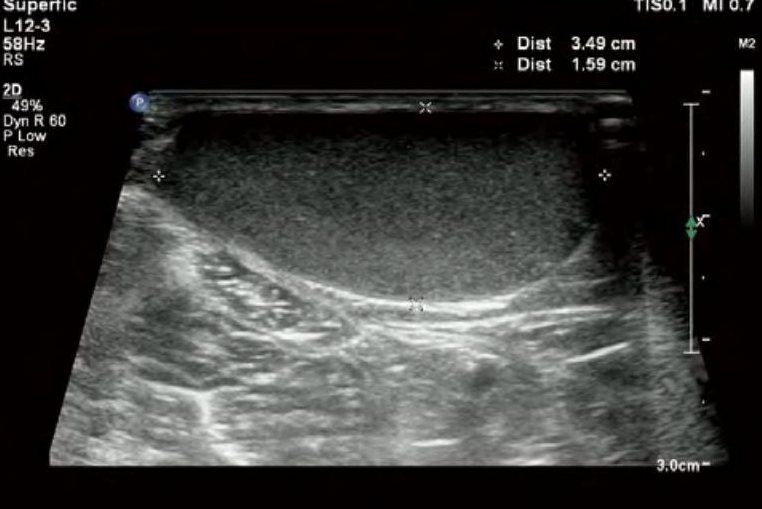

皮脂腺囊肿常好发于头面、背臀等处,多为单发。囊肿呈球形,大小不等,可能压迫周围组织引起不适。表面光滑边界清晰,硬度中等或有弹性、无波动感,常与皮肤有粘连不易推动,但基底可移动。彩超检查可见皮下组织内肿物呈椭圆形或圆形,囊内容物呈密集细小的光点回声,呈粗颗粒状,大部分回声不均匀,囊壁较厚,与周边皮肤界限比较清晰,进行探头加压时会发现囊内有变形现象,部分肿物有抖动、缓慢流动,一般无明显血流征象。